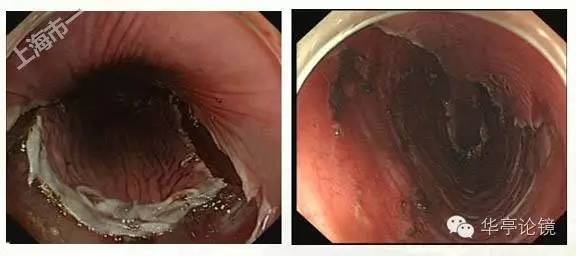

卢戈氏碘染色:病变区多片不染区,形态不规则,见下图。

2015年9月30日,我们市一南院消化内镜团队就此病人实施了ESD术,见下图。

完整组织送检,病理:(食道)粘膜表面鳞状上皮低级别上皮内瘤变,局灶高级别上皮内瘤变,水平及垂直切缘均未见病变残留,见下图。